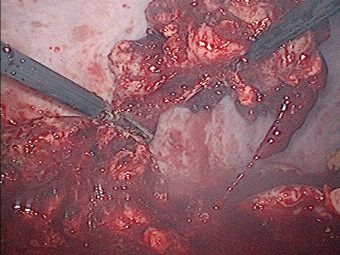

Derrame pleural derecho mas tumor de mediastino posterior